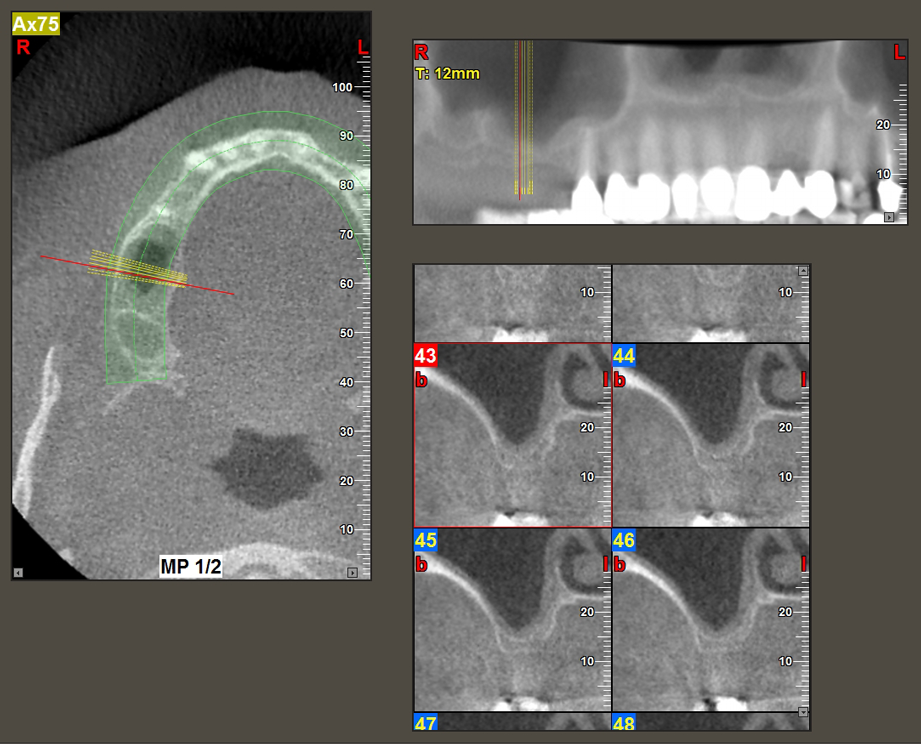

A 49-year-old female patient, a non-smoker and with nothing remarkable in her general medical history, was referred to our oral surgery practice for surgical extraction of tooth 16 and subsequent implantation. After the extraction, the patient experienced mild sinusitis trouble with the resultthat we initially waited six months before carrying out the measure. The residual bone height at the planned implant position measured 3-4 mm (Fig. 1 and 2).